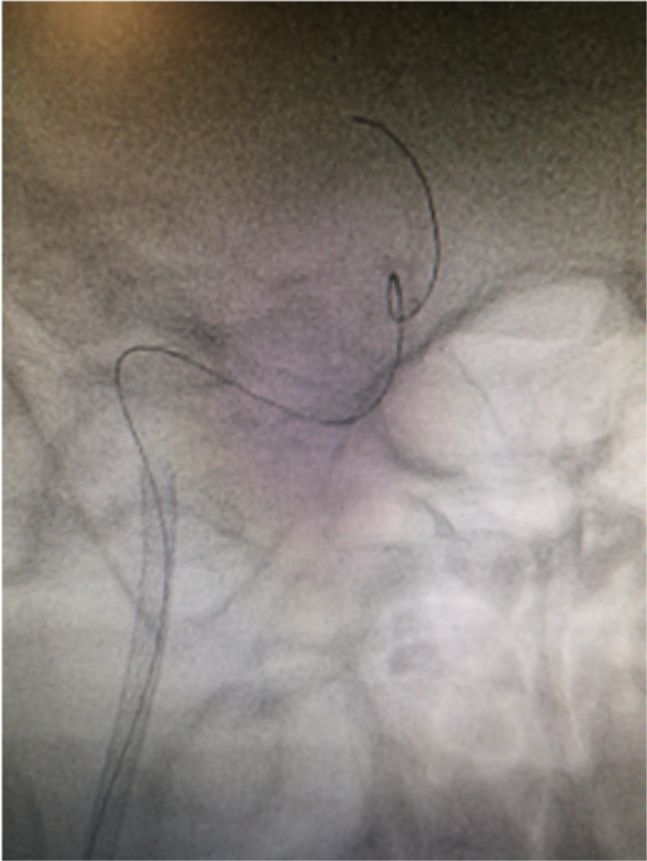

2019-05-24外院头颅MRI+MRA+DWI:右侧基底节区、放射冠、半卵圆中心脑梗死,右侧颈内动脉闭塞(图1)。

图1